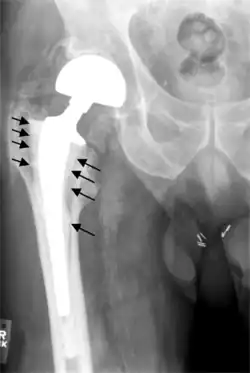

Fracture

Intraoperative fractures may occur. After surgery, bones with internal fixation devices in situ are at risk of periprosthetic fractures at the end of the implant, an area of relative mechanical stress. Post-operative femoral fractures are graded by the Vancouver classification.[32][33]